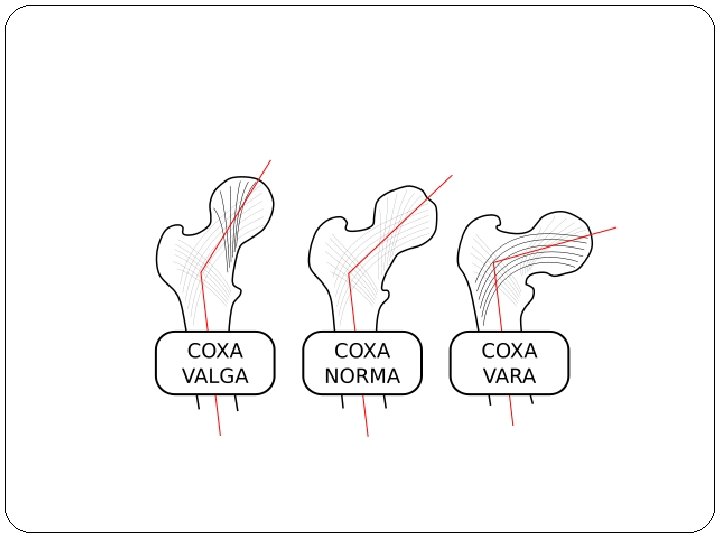

Cont …. Pathology: a. The acetabulum is shallow (shaped like a saucer instead of a cup). b. The femoral head gets dislocated. c. The capsule is stretched and the ligamentum teres becomes elongated and hypertrophied. Two forms of femoral dysplasia are: Coxa vara, in which the femur head grows at too narrow an angle to the shaft. Coxa valga, in which the angle is too wide.